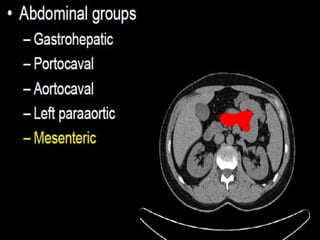

CT cross sectional anatomy.

CT – computedtomography. •Cross-sectional modality with capabilities for multiplanar reconstruction and dynamic imaging to assess vascularity •Tube rotates around the body and a circle of stationary detectors detects the penetrating x-rays forming an image.